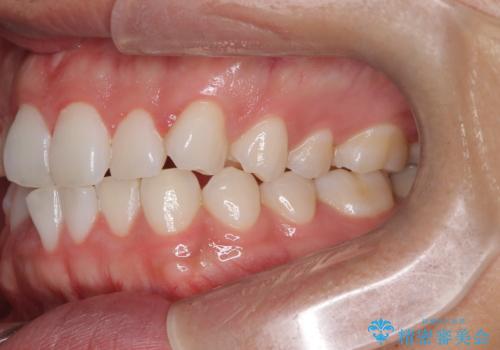

歯のデコボコを治したい|インビザラインで綺麗な歯並びに!|矯正期間は6ヵ月!

- 歯のデコボコが気になるを主訴に来院された患者様です。

インビザラインで歯は抜かずに非抜歯でデコボコを改善しました。

インビザラインで叢生の改善を行いました。

歯は抜かずに、拡大と少しのIPRで並べました。

矯正期間は半年です。

綺麗な歯並びを手に入れ大変ご満足していただきました。